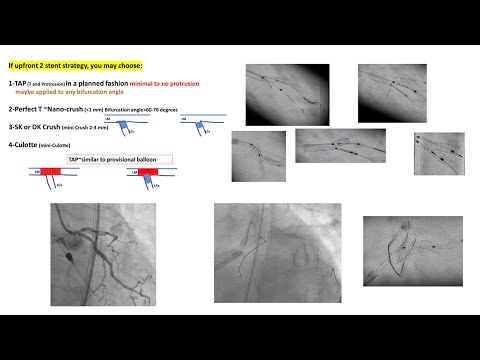

Elective complex approach to Bifurcation PCI: when to consider and how to do it, Dr/ Costa

Live Case 12 - Dedicated Two Stent Strategy via Radial Approach